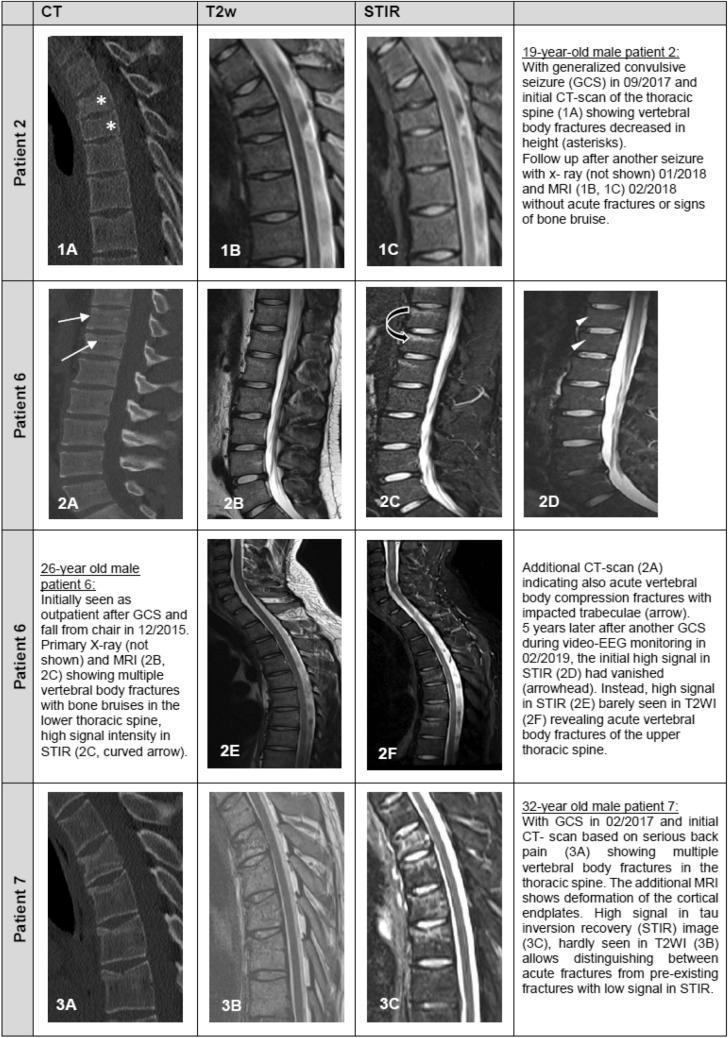

A total of 626 GCSs from 411 patients (mean age: 33.6 years; range 3-74 years; 45.0% female) were analyzed. Severe adverse events (SAEs) such as fractures, joint luxation, corneal erosion, and teeth loosening were observed in 13 patients resulting in a risk of 2.1% per GCS (95% CI 1.2-3.4%) and 3.2% per patient (95% CI 1.8-5.2%). Except for a nasal fracture due to a fall onto the face, no SAEs were caused by falls, and all occurred in patients lying in bed without evidence of external trauma. In seven patients, vertebral body compression fractures were confirmed by imaging. This resulted in a risk of 1.1% per GCS (95% CI 0.5-2.2%) and 1.7% per patient (95% CI 0.8-3.3%). These fractures occurred within the tonic phase of a GCS and were accompanied by a characteristic cracking noise. All affected patients reported back pain spontaneously, and an increase in pain on percussion of the affected spine section.

共分析了来自 411 例患者的 626 次 GCS(平均年龄:33.6 岁;年龄范围 3-74 岁;45.0%为女性)。13 例患者出现严重不良事件(SAE),如骨折、关节脱位、角膜侵蚀和牙齿松动,导致每次 GCS 发生风险为 2.1%(95%CI 1.2-3.4%),每位患者发生风险为 3.2%(95%CI 1.8-5.2%)。除了因摔倒面部导致的鼻骨骨折外,没有因跌倒引起的 SAE,所有发生在未受外伤的卧床患者。7 例患者经影像学证实椎体压缩性骨折。导致每次 GCS 发生风险为 1.1%(95%CI 0.5-2.2%),每位患者发生风险为 1.7%(95%CI 0.8-3.3%)。这些骨折发生在 GCS 的强直期,并伴有特征性的爆裂声。所有受影响的患者均自发报告背痛,并在叩诊受影响的脊柱节段时疼痛加重。